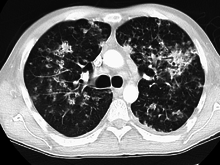

Tuberculosis of the lungs

Testing for miliary tuberculosis is conducted in a similar manner as for other forms of tuberculosis, although a number of tests must be conducted on a patient to confirm diagnosis.[5] Tests include chest x-ray, sputum culture, bronchoscopy, open lung biopsy, head CT/MRI, blood cultures, fundoscopy, and electrocardiography.[11] The tuberculosis (TB) blood test, also called an Interferon Gamma Release Assay or IGRA, is a way to diagnose latent TB. A variety of neurological complications have been noted in miliary tuberculosis patients—tuberculous meningitis and cerebral tuberculomas being the most frequent. However, a majority of patients improve following antituberculous treatment. Rarely lymphangitic spread of lung cancer could mimic miliary pattern of tuberculosis on regular chest X-ray. [16]